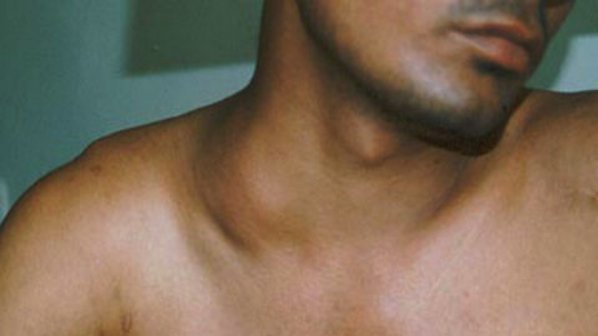

УЗИ лимфоузлов при лимфоме Ходжкина